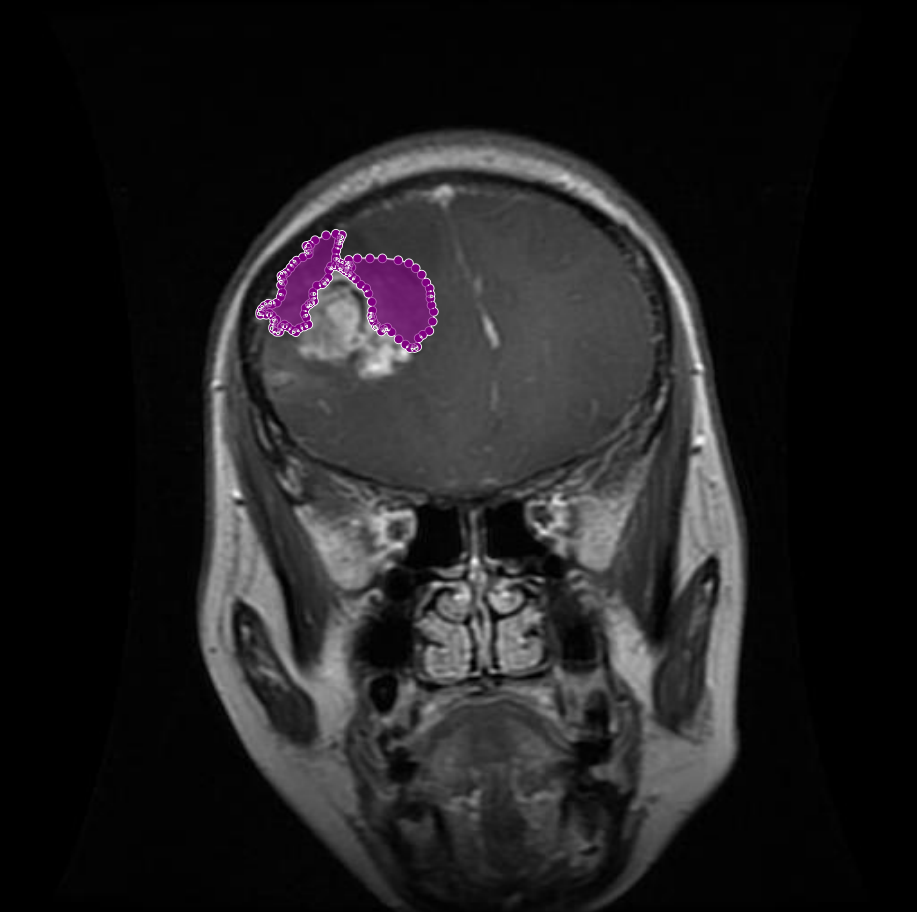

Figure 6: Samples of partial-region overannotations. The red area indicates regions that were initially marked as tumorous but were later identified by the radiologist and physician as non-tumorous.

In other instances, certain areas that were mistakenly included as part of the tumor region were refined based on radiologist and physician feedback. These areas, though visually similar to tumor tissue, were determined to be non-tumorous upon closer examination. As illustrated in Figure 6, the removal of these incorrect segments resulted in more precise tumor masks and enhanced the reliability of the dataset.